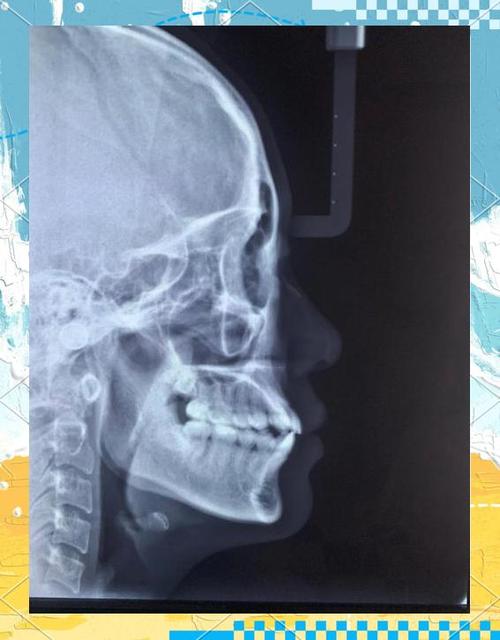

北大口腔正畸科的治疗流程严格遵循科学规范,确保每一步都精准高效,初诊阶段,医生会通过详细的口腔检查(包括视诊、探诊)、X光片(全景片、头颅侧位片)、CBCT影像分析以及牙齿模型制作,全面评估患者的牙齿排列、颌骨关系、面部软组织形态及口腔健康状况,对于儿童患者,还会结合生长发育预测,判断是否存在早期矫治的必要性,方案设计阶段,医生会基于患者的年龄、错颌类型、美观需求及全身健康状况,制定个性化的治疗计划,并通过数字化模拟技术向患者展示治疗后的预期效果,充分沟通后确定最终方案,治疗过程中,医生会根据牙齿移动的规律定期调整矫治器,通常每4-6周复诊一次,同时密切观察患者的口腔卫生状况和牙周健康,及时处理可能出现的问题,拆除矫治器后,患者需严格佩戴保持器,以巩固治疗效果,防止复发,科室会为患者制定长期的保持计划,并通过定期复查确保稳定。